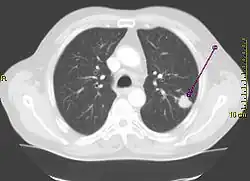

Klasický rentgenový snímek hrudníku vykazující karcinom plic (označen šipkou) | |

Provedení rentgenu hrudníku je jedním z prvních kroků při vyšetření osoby trpící symptomy, jež by mohly naznačovat karcinom plic. Může odhalit přítomnost tumoru, rozšíření mezihrudí (naznačující, že tumor napadl lymfatické uzliny), atelektázu (kolaps), konsolidaci plic (pneumonii) nebo fluidothorax.[5] Ke zjištění detailnějších informací o typu a rozsahu onemocnění se typicky používá CT snímkování. Bronchoskopie nebo CT snímkováním řízená biopsie často slouží k odebrání vzorku tumoru pro účely histopatologie.[13]

Rakovina plic se na rentgenu hrudníku často objevuje jako solitární plicní uzel. Diferenciální diagnostika však uvádí řadu dalších onemocnění s podobným symptomem. Stejný příznak může způsobit i tuberkulóza, plísňové infekce, metastatická rakovina nebo organizující se pneumonie. Mezi méně běžné příčiny solitárního plicního uzlu patří hamartomy, bronchogenní cysty, adenomy, arteriovenózní malformace, plicní sekvestrace, revmatoidní uzlíky, Wegenerova granulomatóza nebo lymfom.[57] Karcinom plic může být odhalen i náhodně jako solitární plicní uzel na rentgenovém nebo CT snímku hrudníku pořízeném pro jiný, nesouvisející účel.[58] Definitivní diagnóza karcinomu plic se stanovuje na základě histologického vyšetření podezřelé tkáně z hlediska klinického a radiologického.[1]